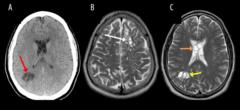

Fuente de la imagen, American Journal of Case Reports

Estas imágenes permitieron detectar la presencia de las larvas de tenia en el cerebro del paciente.

Al realizarle tomografías, los médicos encontraron la presencia de numerosos quistes en el cerebro que, según luego comprobaron con estudios posteriores, en realidad eran larvas de tenia que se habían instalado en su cerebro y que eran las causantes de una infección conocida como neurocisticercosis.